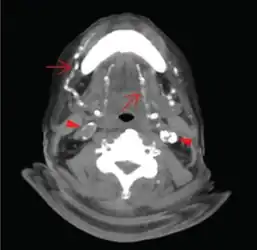

Microphotography of arterial wall with calcified (violet colour) atherosclerotic plaque (haematoxylin & eosin stain)